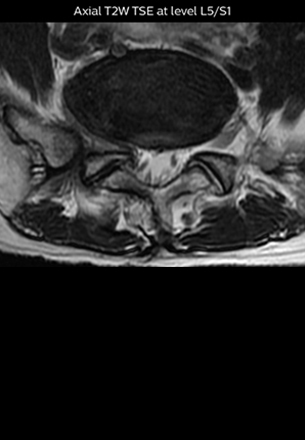

The key concept in MR neurography, Dr. Yabuki stresses, is the ability to directly visualize spinal nerves, versus inferring the presence of pathology indirectly. “Before NerveVIEW, we estimated compression of the nerve by looking for the presence or absence of fat signal on other MR images,” he says.

“For example, in sagittal images, when the presence of fat is observed in the intervertebral foramen, it suggests that there is a margin around the nerve. Similarly, the absence of fat indicates that the nerve is being compressed. So, we used to deduce nerve compression indirectly. With NerveVIEW, however, we can observe the condition of the nerves directly, regardless of the presence or absence of fat. We always prefer such direct observation of anatomy over having to make an inference about it.”

“The intra-luminal signal of veins, especially around the intervertebral space, can be suppressed well with NerveVIEW. As a result, we can easily observe the detailed nerve structure around the posterior ganglion,” he says. “This is why we use 3D NerveVIEW for intraforaminal stenosis and extraforaminal stenosis/herniation (lateral disc herniation). On the other hand, if herniation is suspected to exist inside the dorsal root ganglion (DRG), balanced TFE or ProSet-FFE is applied. NerveVIEW is not suitable for evaluating the median type of herniation.” The SE-EPI DWI-based method for MR neurography works well for large FOV exams like whole-body MRI, but focal examination of nerves is often limited by the attainable spatial resolution (both inplane and slice direction) and geometric distortion. “3D NerveVIEW achieves higher in-plane resolution – close to our other routine spine sequences – and the source images can be used instead of adding a fat-suppressed T2-weighted sequence,” Tanji says.